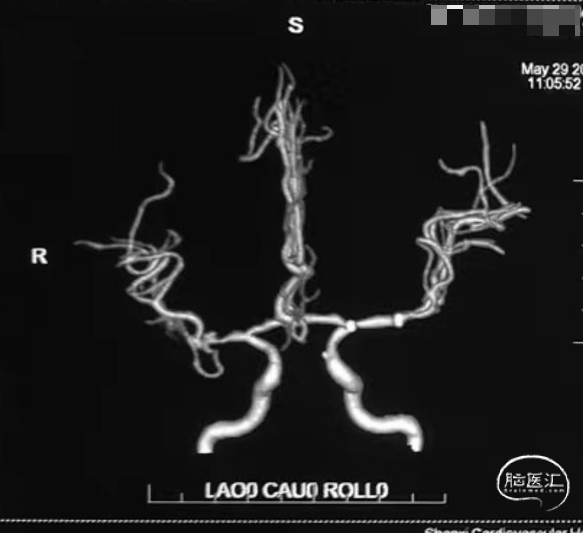

核磁MRA提示:双侧大脑中动脉狭窄。

➢脑血管DSA

➢RCCA

➢LCCA

➢术前诊断:

左侧大脑中动脉M1段重度狭窄

右侧大脑中动脉M1段中度狭窄